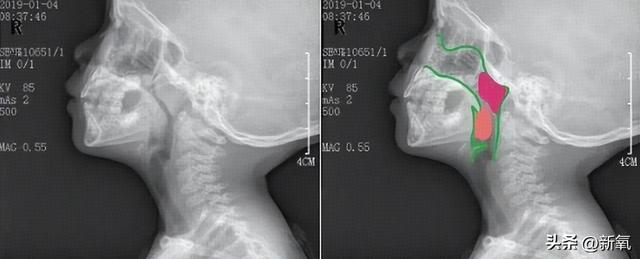

2️⃣鼻咽部侧位X片检查

检查过程:拍摄侧位X片;

报告结果:医院出具的报告中会有A/N的比值结果,一般会精确到小数点后一位,像0.7、0.8、0.9;更精确的会到小数点后两位,像0.75、0.8、0.85。

绿色:正常上呼吸道,红色:肥大的腺样体,橙色:肿大的扁桃体